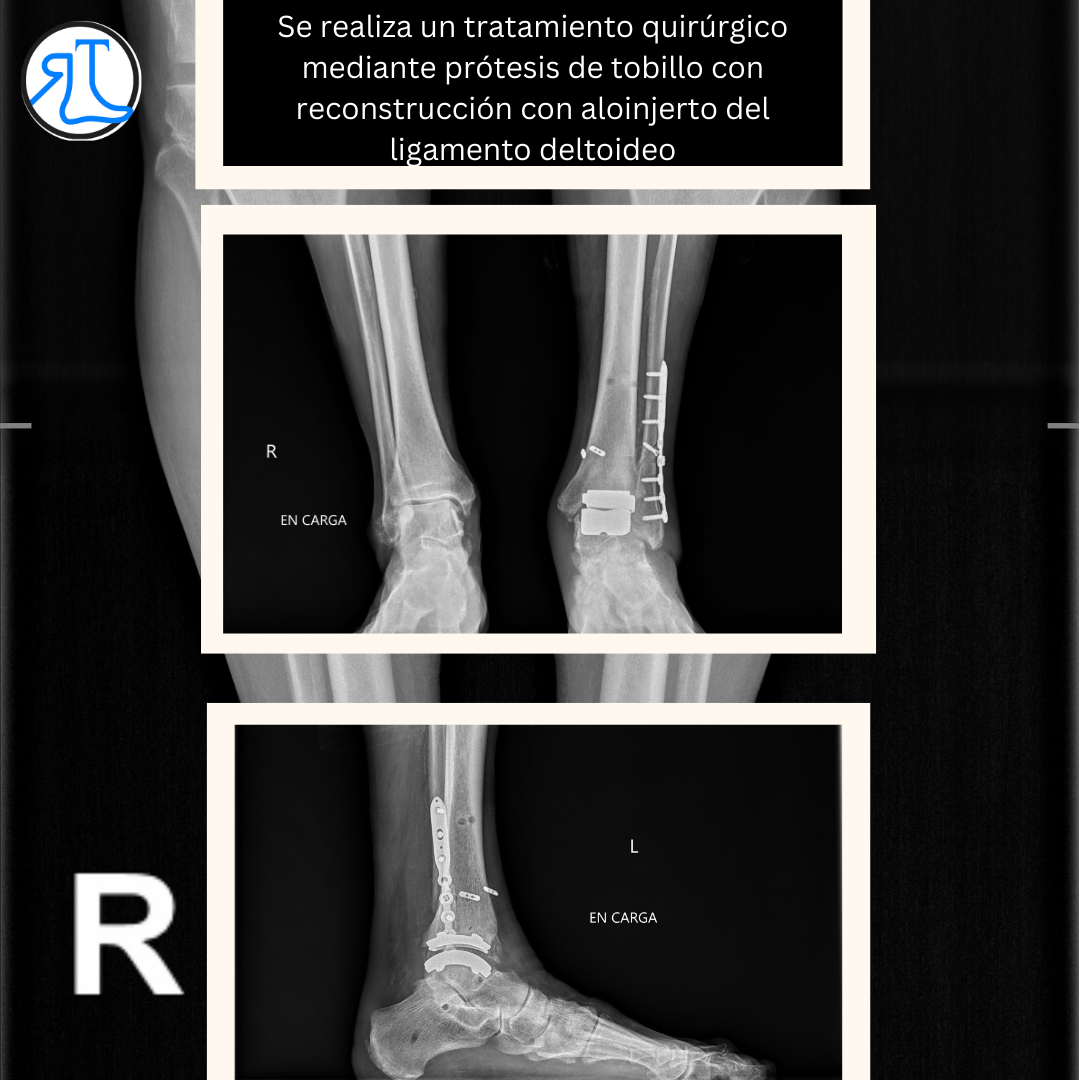

El paciente era muy reacio a perder la movilidad de su tobillo (muy conservada) por lo que se decidió implantar una prótesis de tobillo junto con una reconstrucción de ligamento deltoideo mediante el uso de un aloinjerto.

El tipo de prótesis implantada obliga a una inmovilización en el postoperatorio inmediato pero pese a ello el paciente ha recuperado una movilidad no dolorosa que le permite desarrollar una actividad plena.